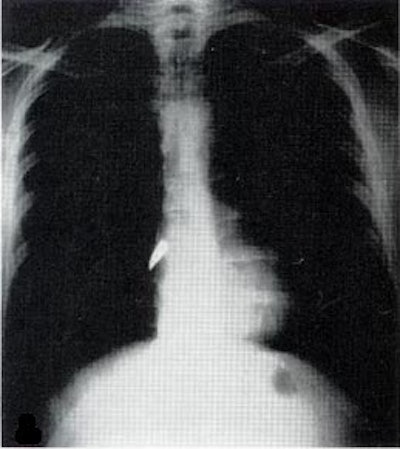

X-rays, a type of electromagnetic radiation, had been discovered in 1895 by Curie’s fellow Nobel laureate, Wilhelm Roentgen. As I describe in my book Strange Glow: The Story of Radiation, almost immediately after their discovery, physicians began using x-rays to image patients' bones and find foreign objects -- like bullets.

X-ray of a bullet in the heart. Image from Wikimedia Commons.But at the start of the war, x-ray machines were still found only in city hospitals, far from the battlefields where wounded troops were being treated. Curie's solution was to invent the first "radiological car" -- a vehicle containing an x-ray machine and photographic darkroom equipment -- which could be driven right up to the battlefield where army surgeons could use x-rays to guide their surgeries.